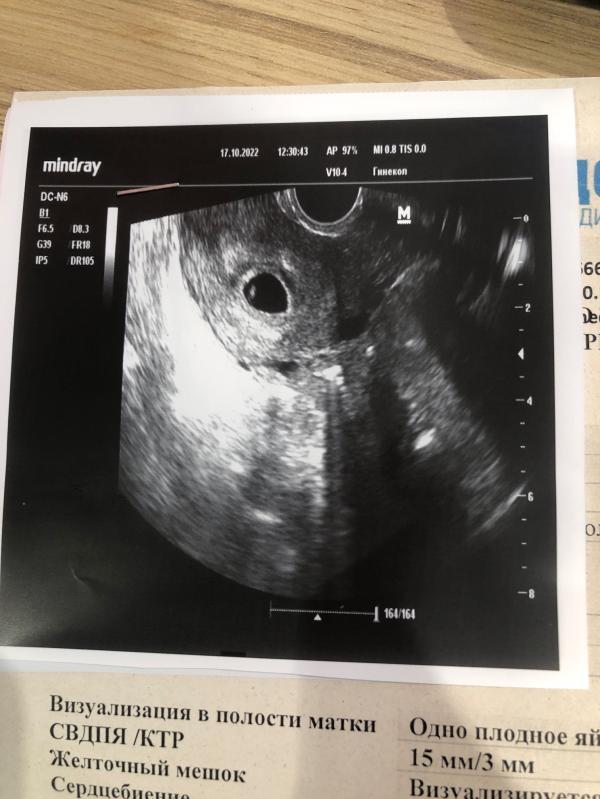

Первая фотография 🥰

Сегодня 11 день задержки, увидели эмбрион, сердцебиение